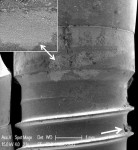

Damage to the cement layer and implant surfaces was visually apparent between the threads of the implants treated with the diode laser (Figure 10 and Figure 12). Additionally, SEM revealed areas of heat-induced titanium surface melting and cavitational defects with melting of residual cement (Figure 11 and Figure 13). SEM examination of implants subjected to the diode + piezo scaler protocol showed chipping, smearing, and flattening of the implant threads.

The post-treatment SEM images revealed that surface damage varied and included scratching, flattening, smearing, and chipping of the crests of the implant threads. Additionally, both visually and under SEM, the diode laser, when used as a monotherapy, showed localized areas of carbonization and cement surface damage due to excessive heat.When used as a dual therapy with the piezo scaler, less damage was evident as the diode laser was not used alone for the total decontamination time. Although the damages noted might preclude osseointegration or soft-tissue adherence at specific sites on an implant, extensive damage that might interfere with re-osseointegration of an entire implant surface was not observed using any of the test instruments at the prescribed settings (Table 2).